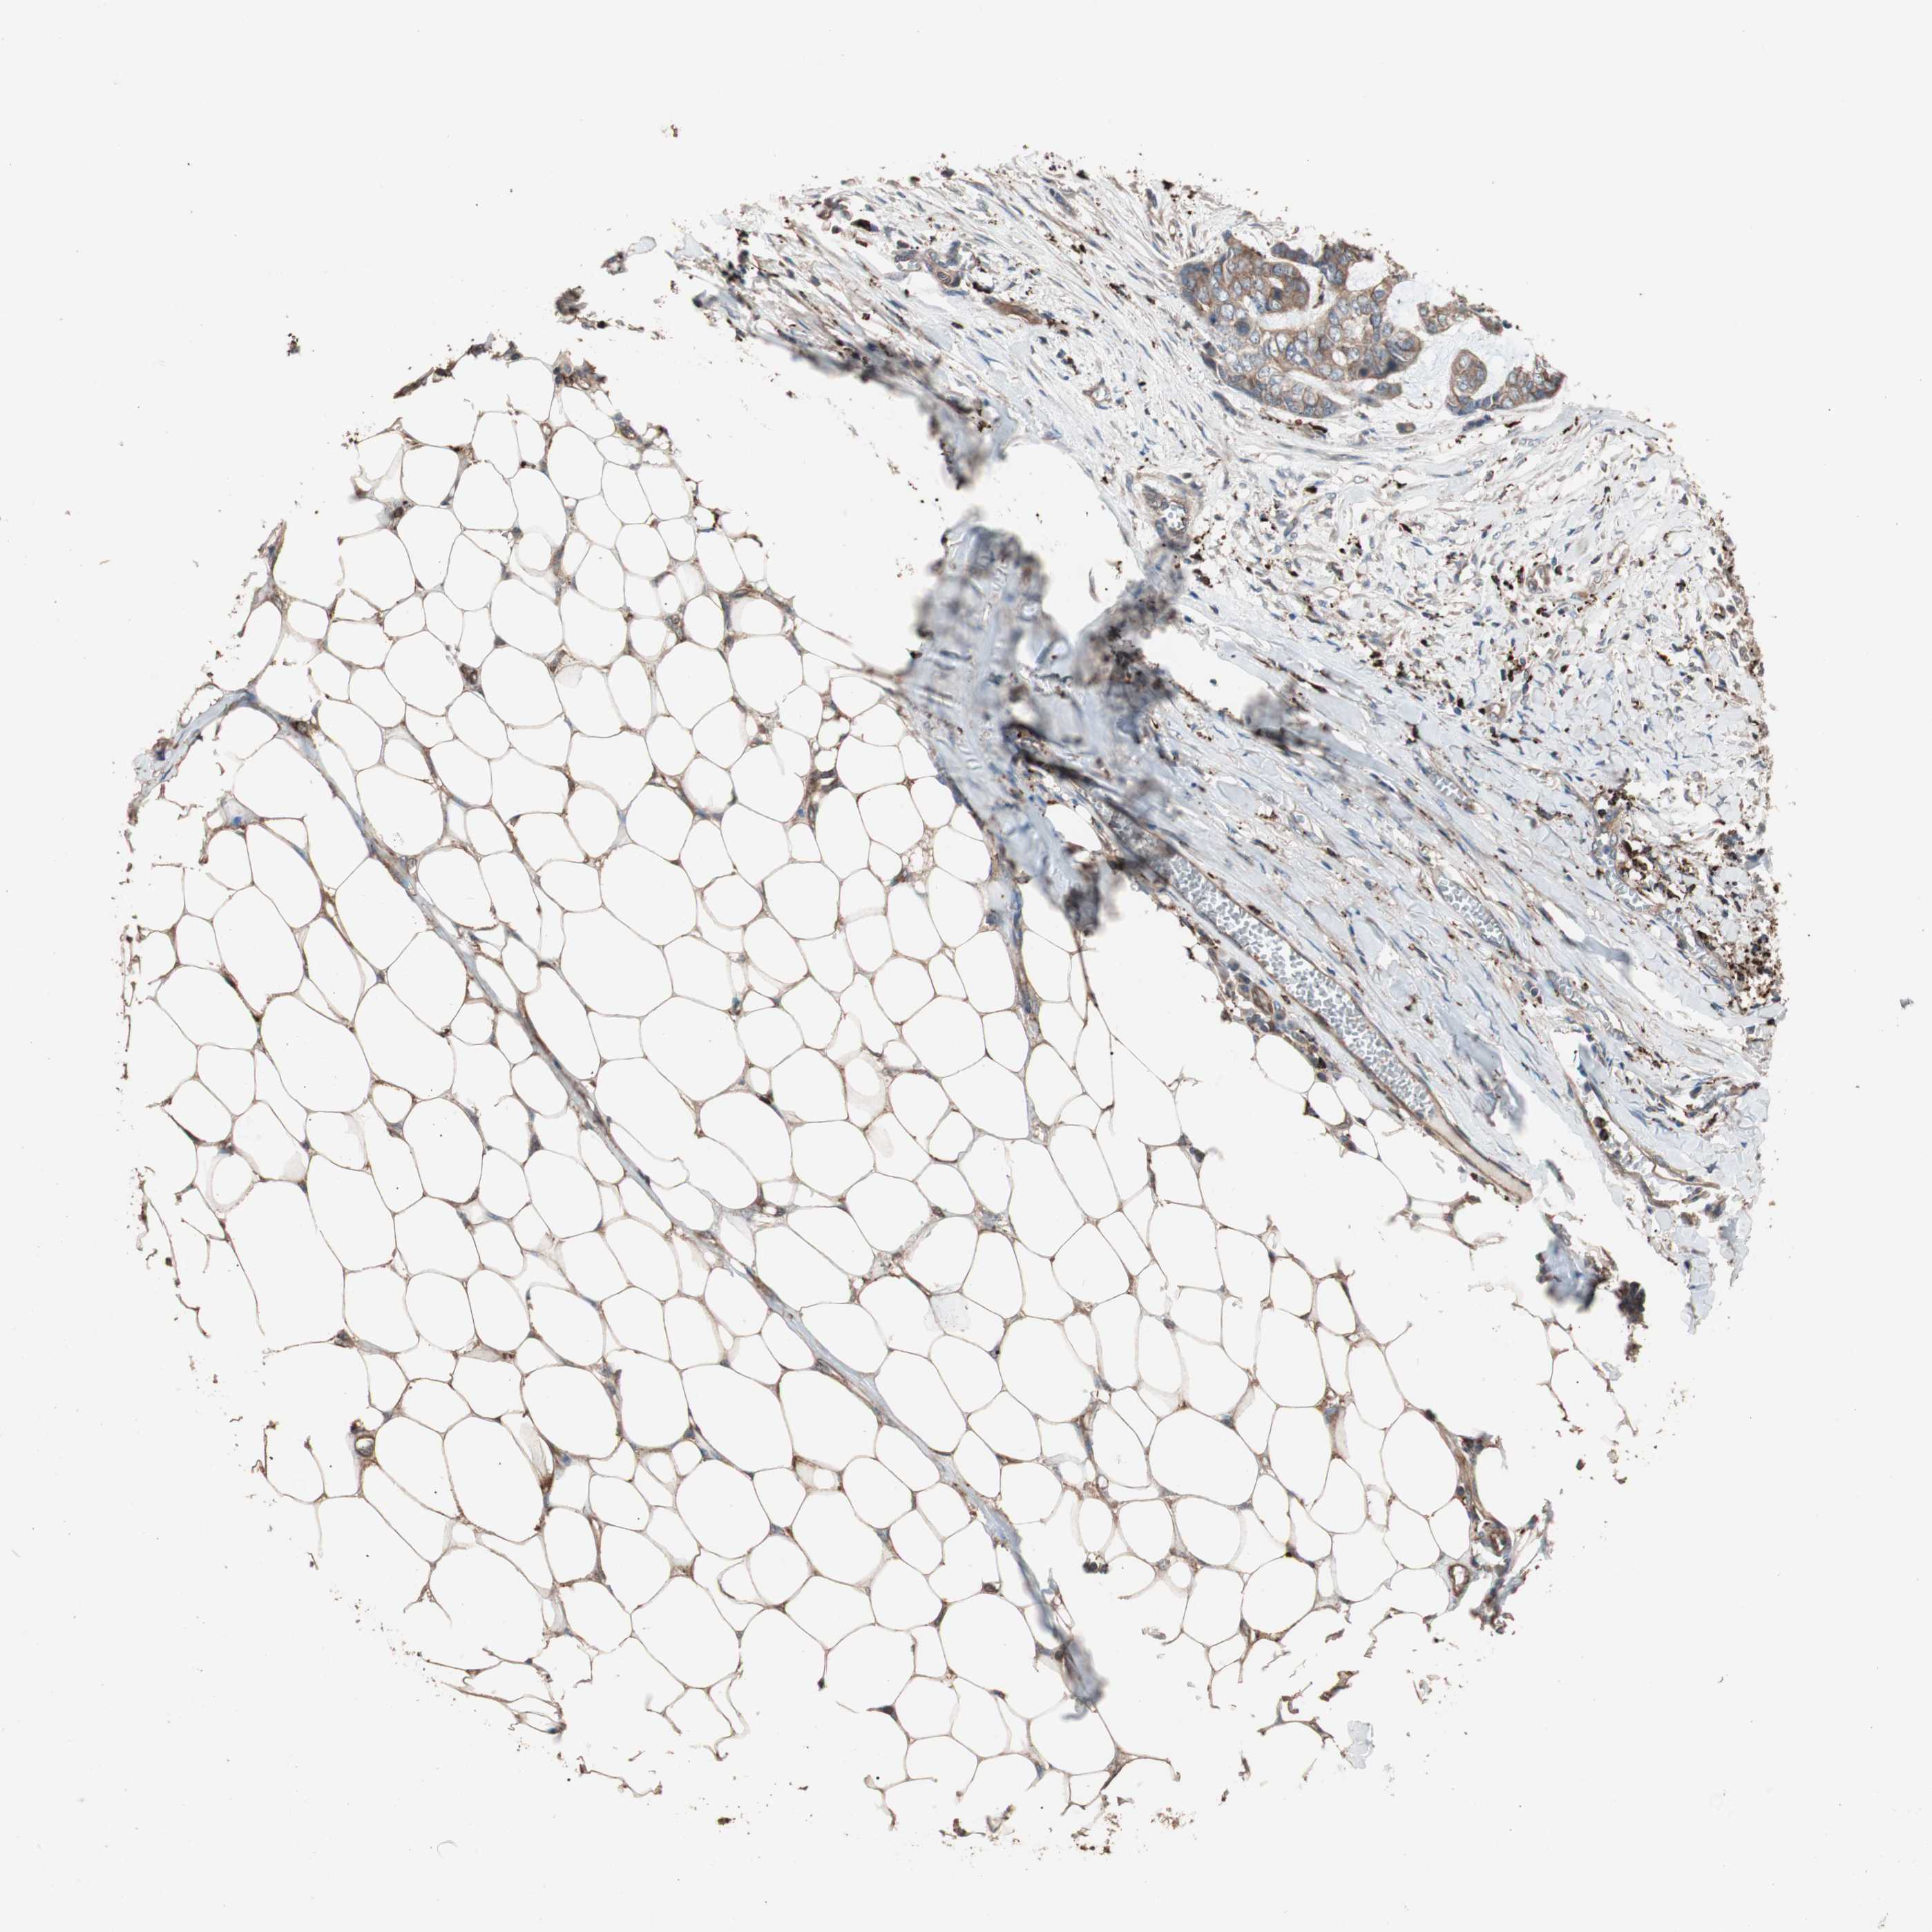

SKIN CANCER - Protein expressioni

A mouse-over function shows sample information and annotation data. Click on an image to view it in a full screen mode. Samples can be filtered based on level of antibody staining by selecting one or several of the following categories: high, medium, low and not detected. The assay and annotation is described here.

Antibody stainingi

Antibody staining in the annotated cell types in the current human tissue is reported as not detected, low, medium, or high, based on conventional immunohistochemistry profiling in selected tissues. This score is based on the combination of the staining intensity and fraction of stained cells.

Each image is clickable and will lead to virtual microscopy that enables deeper exploration of all samples and also displays staining intensity scores, fraction scores and subcellular localization as well as patient and tissue information for each sample.

Antibody HPA006543

Squamous cell carcinoma, metastatic, NOS

Basal cell carcinoma